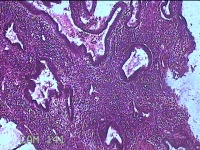

性别

女

年龄

41岁

临床诊断

异常子宫出血(无排卵型子宫出血) 子宫肌瘤

一般病史

阴道流血12天。

标本名称

宫腔内容物

大体所见

灰白暗红色不规则碎组织2.5x2x0.8cm一堆。

图2